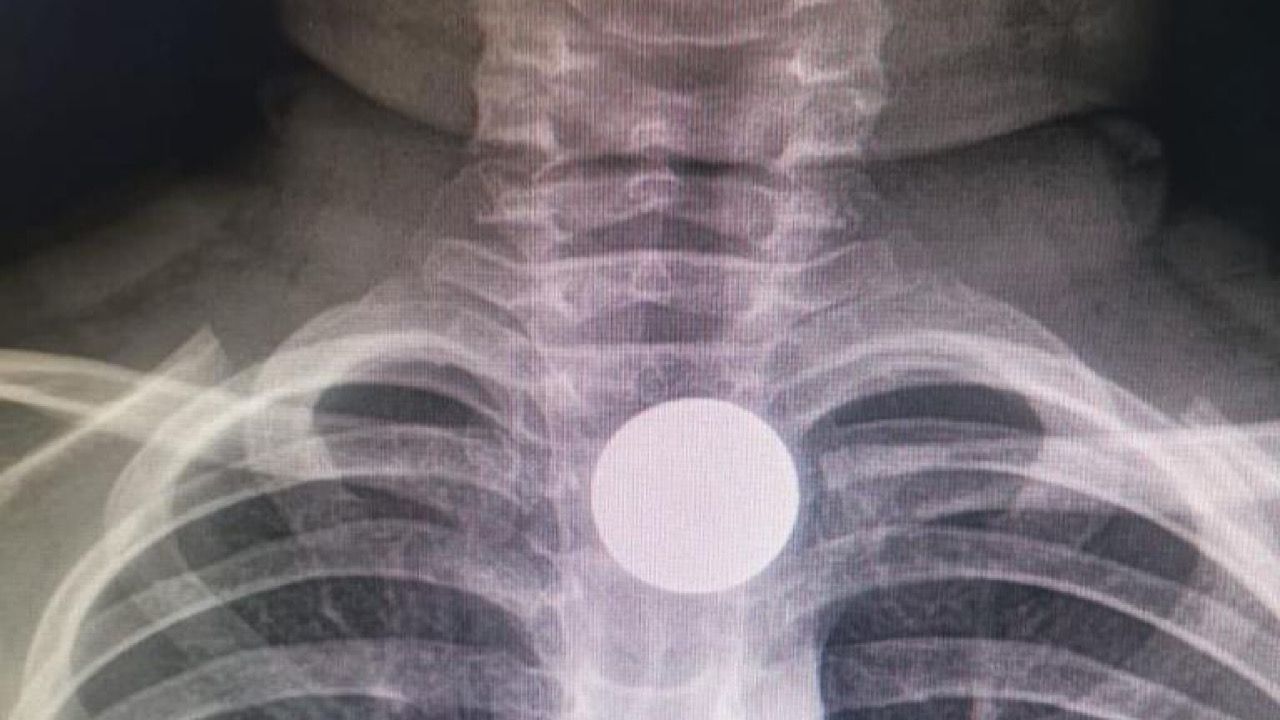

تفاصيل انقاذ حياة طفل في الخفجي ابتلع قطعة معدنية